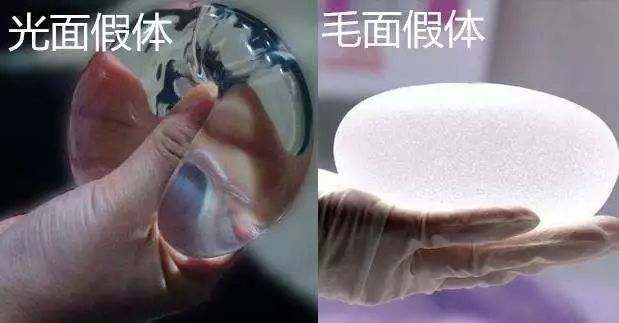

假体隆胸整形手术主要是将假体植入到胸部的部位,使得胸部变得浑圆饱满起来,从而达到了隆胸整形的目的。

假体隆胸整形手术,通常都是不会有什么危险的,因为假体隆胸整形手术,已经有几十年的发展历史了,发展到现在,整形技术已经是越来越成熟了,而且是国批准可以进行的整形手术之一。

但是求美者们一定要选择在正规医院里面进行隆胸整形手术哦,因为在那些不正规的没有资质的小医院里面进行隆胸整形手术的话,他们的医生技术水平没有保障,而且他们都假体材料可能也是假冒伪劣产品,更可能没有正规的渠道来源,和大医院里面通常都是跟品牌商合作的,拿到的都是一手的产品,安全有保障。